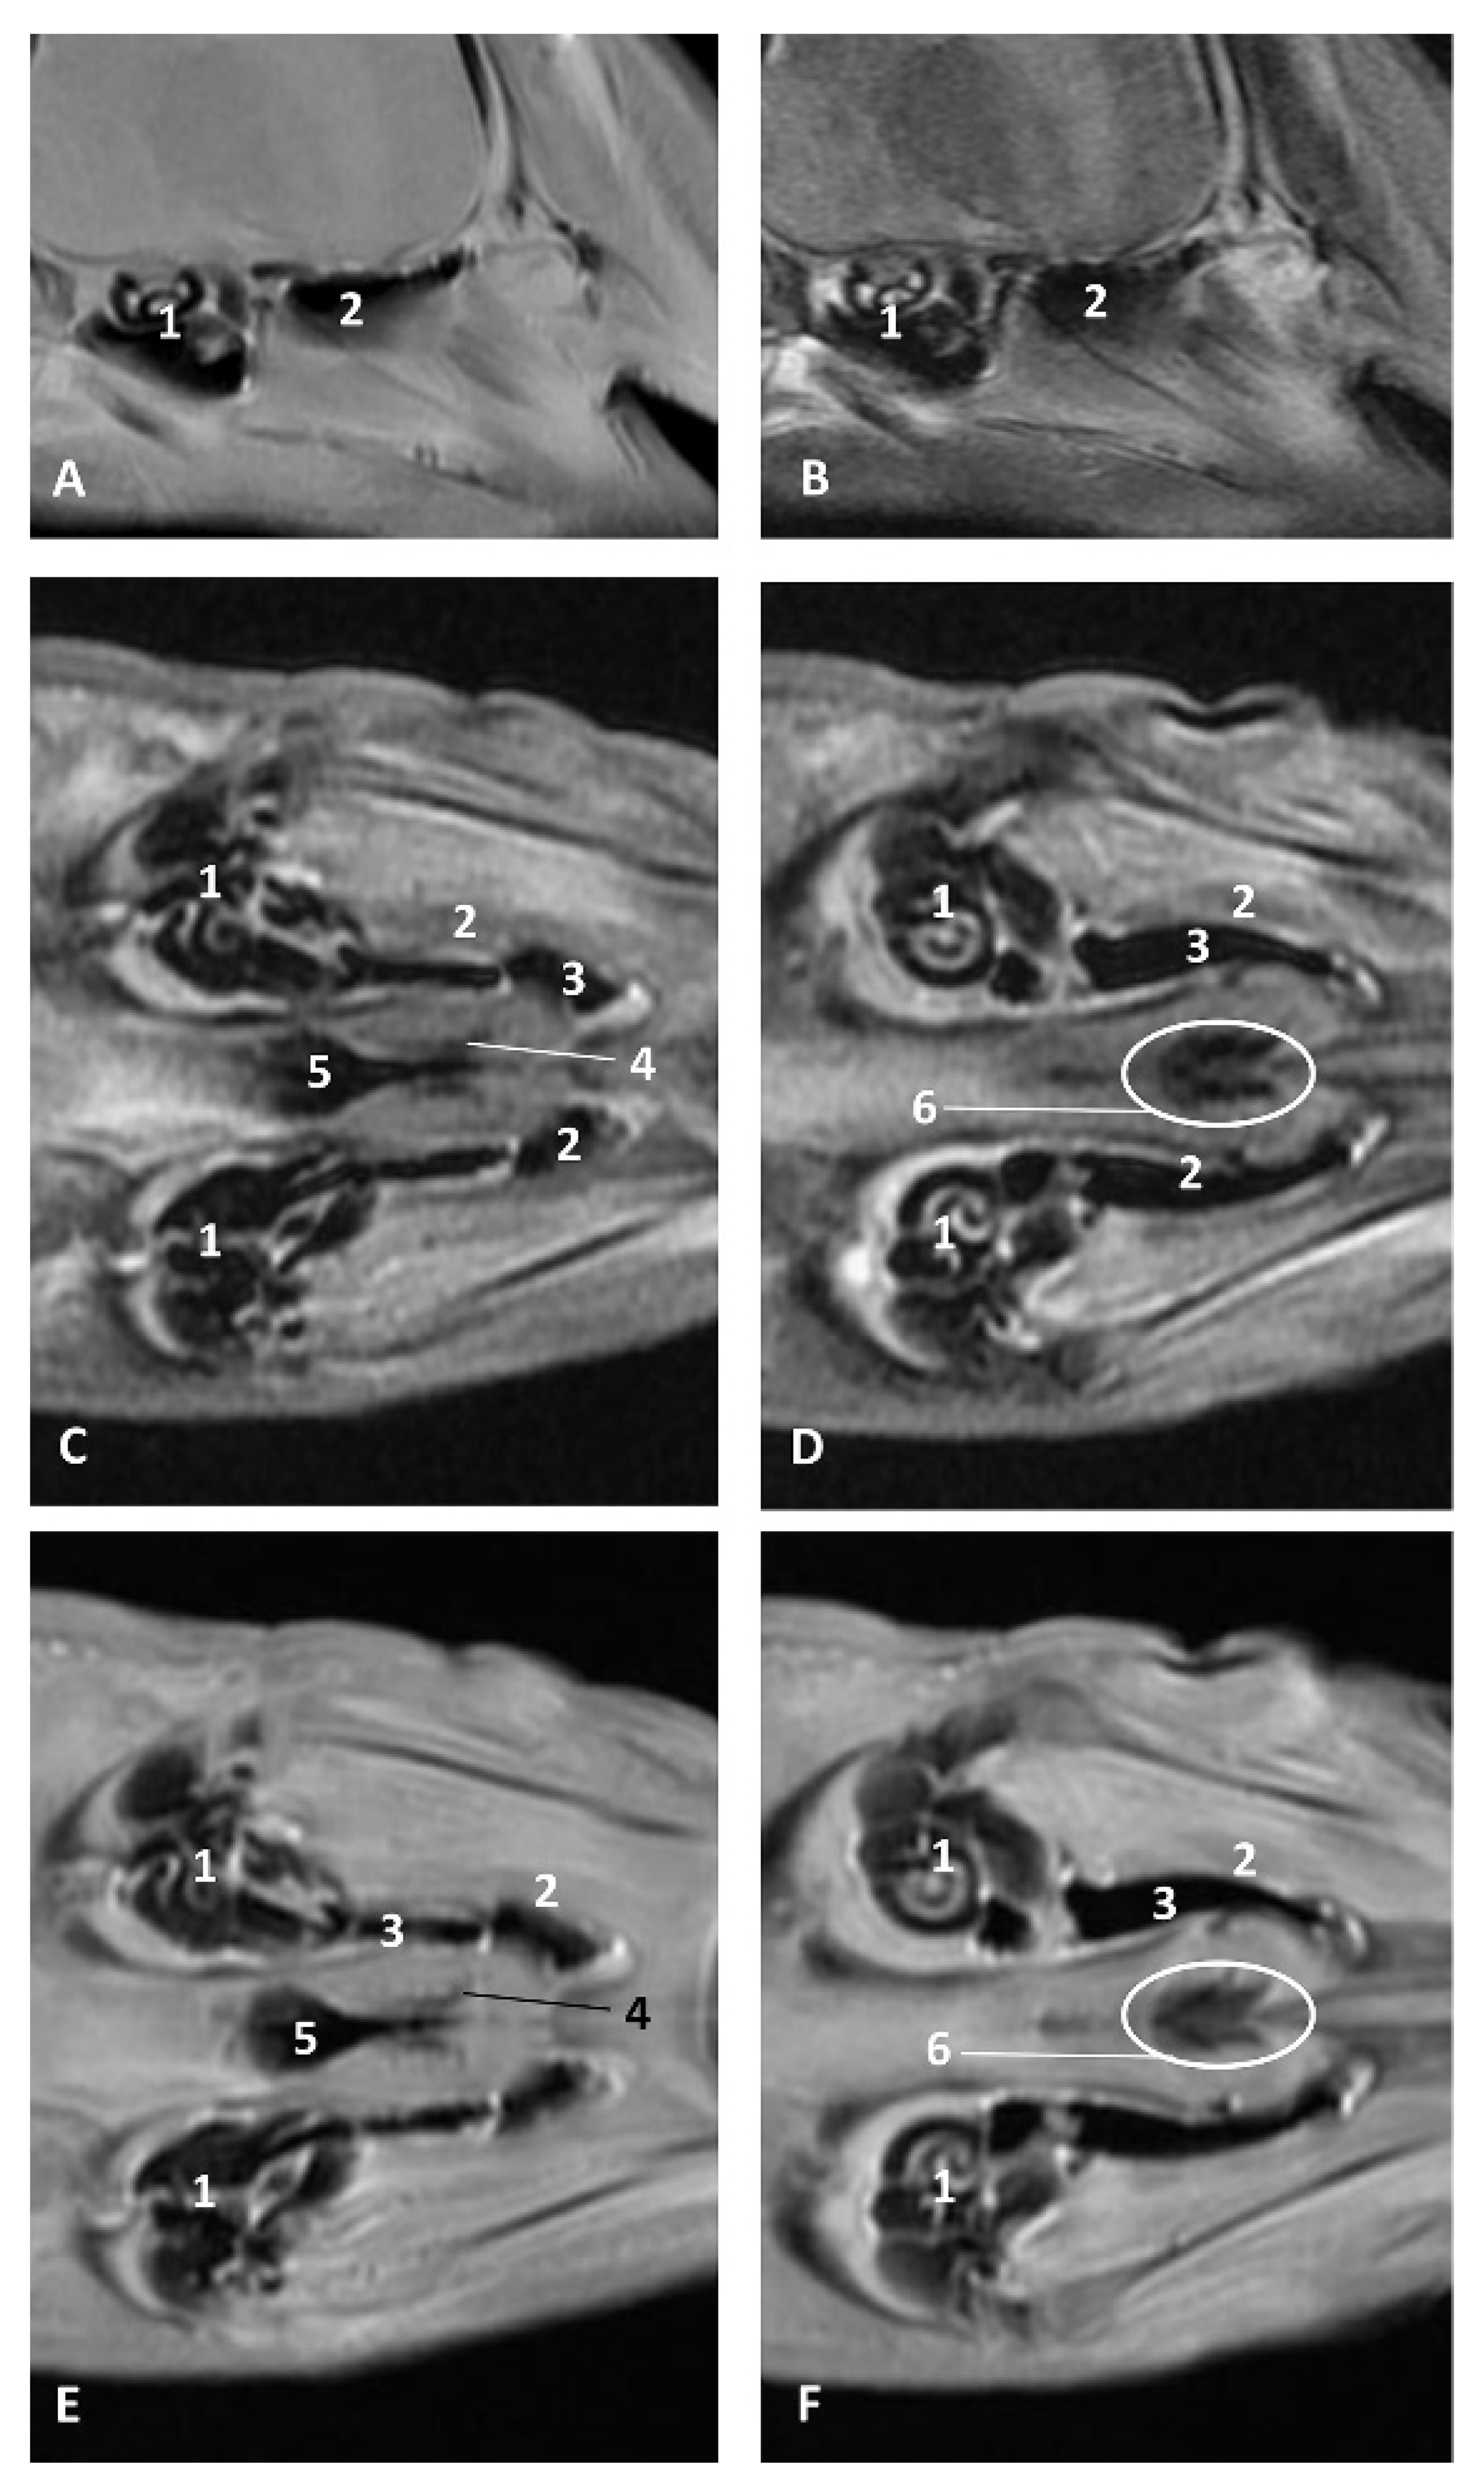

The three coronal sections, in a newborn Stenella coeruleoalba (scomu2), extend from the floor (Figure 34A) to the roof of the oral and pharyngeal cavities (Figure 34B,C). In these images it was possible to observe the proximity to the mandible channel tissue and the pharyngeal orifices of the auditory tubes crossing the pharyngeal muscles. It is easy to medially differentiate the air area (near the auditory tube and nasopharynx and laterally to the cribriform area) (Figure 34).

Figure 34.

(A–C) Coronal sections of head at level of eyes, ear, pharyngeal and oral cavity. These three sections show the extension and connection between the pterygopalatine recess (pterygoid sinus) and the PDAT and between the nasopharynx and PDAT. (A,B) Dorsal view (C) Ventral view. scomu2. 1, Middle and inner ear; 2, Pharyngeal orifices of the auditory tube; 3, Pharyngeal diverticulum of the auditory tube: air area; 4, Pharyngeal diverticulum of the auditory tube: vascular area; 5, Vomer and choanas; 6, Pharyngeal muscles; 7, Piriform recess; 8, Laryngeal cartilages: aditus laryngis; 9, Hard palate (maxillary bones); 10, Tongue (sectioned) 11, Mandibles; 12, Labial vestibule; 13, Oral cavity.

The two sagittal sections in a juvenile Stenella coeruleoalba (scomu3) were made para-sagittally at the level of the ear. It shows that this area (PDAT) extends rostrally to the inner and middle ear crossing below the basal bones of the cranium to arrive to the pterygopalatine recess (pterygoid sinus) and finish dorsally at the maxillopalatine fossa (Figure 35).

Figure 35.

(A,B) Detailed serial sagittal sections at level of the pharyngeal diverticulum of the auditory tube with an anfractuous mucosa filled with a heterogeneous content. It extends up to the maxillopalatine fossa rostral to the eyeball. scomu3. 1, Middle and inner ear; 2, Pharyngeal diverticulum of the auditory tube; 3, Occipital bone: basilar part; 4, Basisphenoid bone; 5, Presphenoid and ethmoid bones; 6, Pterygoid bone; 7, Palatine bone; 8, Maxilopalatine fossa (pterygopalatine fossa in domestic mammals); 9, Pterygopalatine recess (pterygoid sinus).